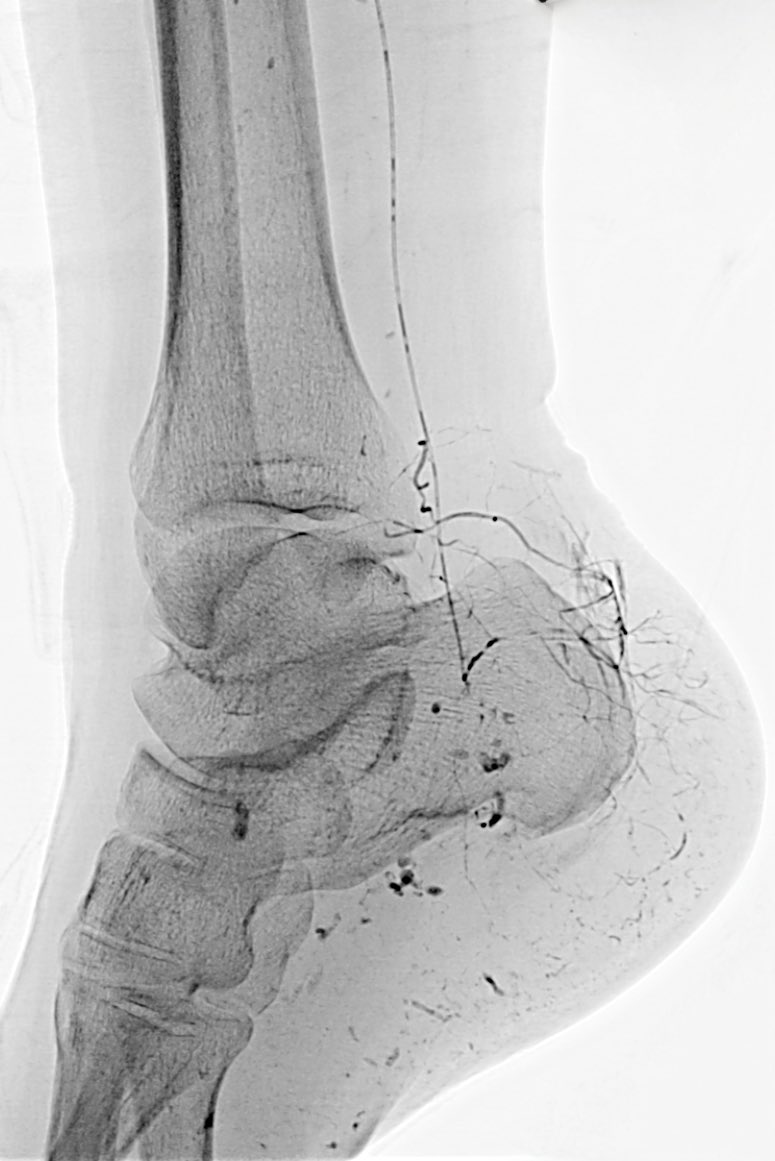

Case 124: with @BhaveshPopat7 @DrAntariksh Dr Vaibhav T . Beauty of conventional Lipiodol TACE - for a single well defined LR-5 lesion . #irad #MedTwitter #meded #medx @_backtable @SIRspecialists @SIRRFS @SIR_ECS